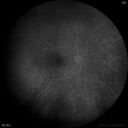

46 year old female - Her original reason for an eye examination was that she had been in a car accident. Then she saw that the vision was blurry in just the left eye. Prior to that she had no known vision changes. Since the accident she notices that her vision is better and her headaches are getting less bothersome.

PMhx benign, Meds: none

VA OD: Dcc20/20

VA OS: Dcc20/25

IOP: TP: OD:9 OS:9